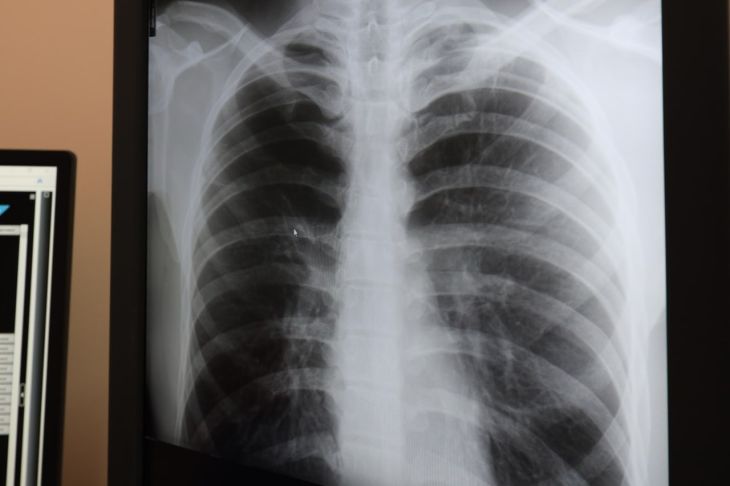

«Надо понимать, что бронхиальная астма — хроническое заболевание дыхательной системы: из-за постоянного воспаления слизистая оболочка бронхов отекает, их просвет сужается. Это затрудняет дыхание, вызывает одышку, кашель, свистящие хрипы, чувство заложенности в груди», — пояснила врач.